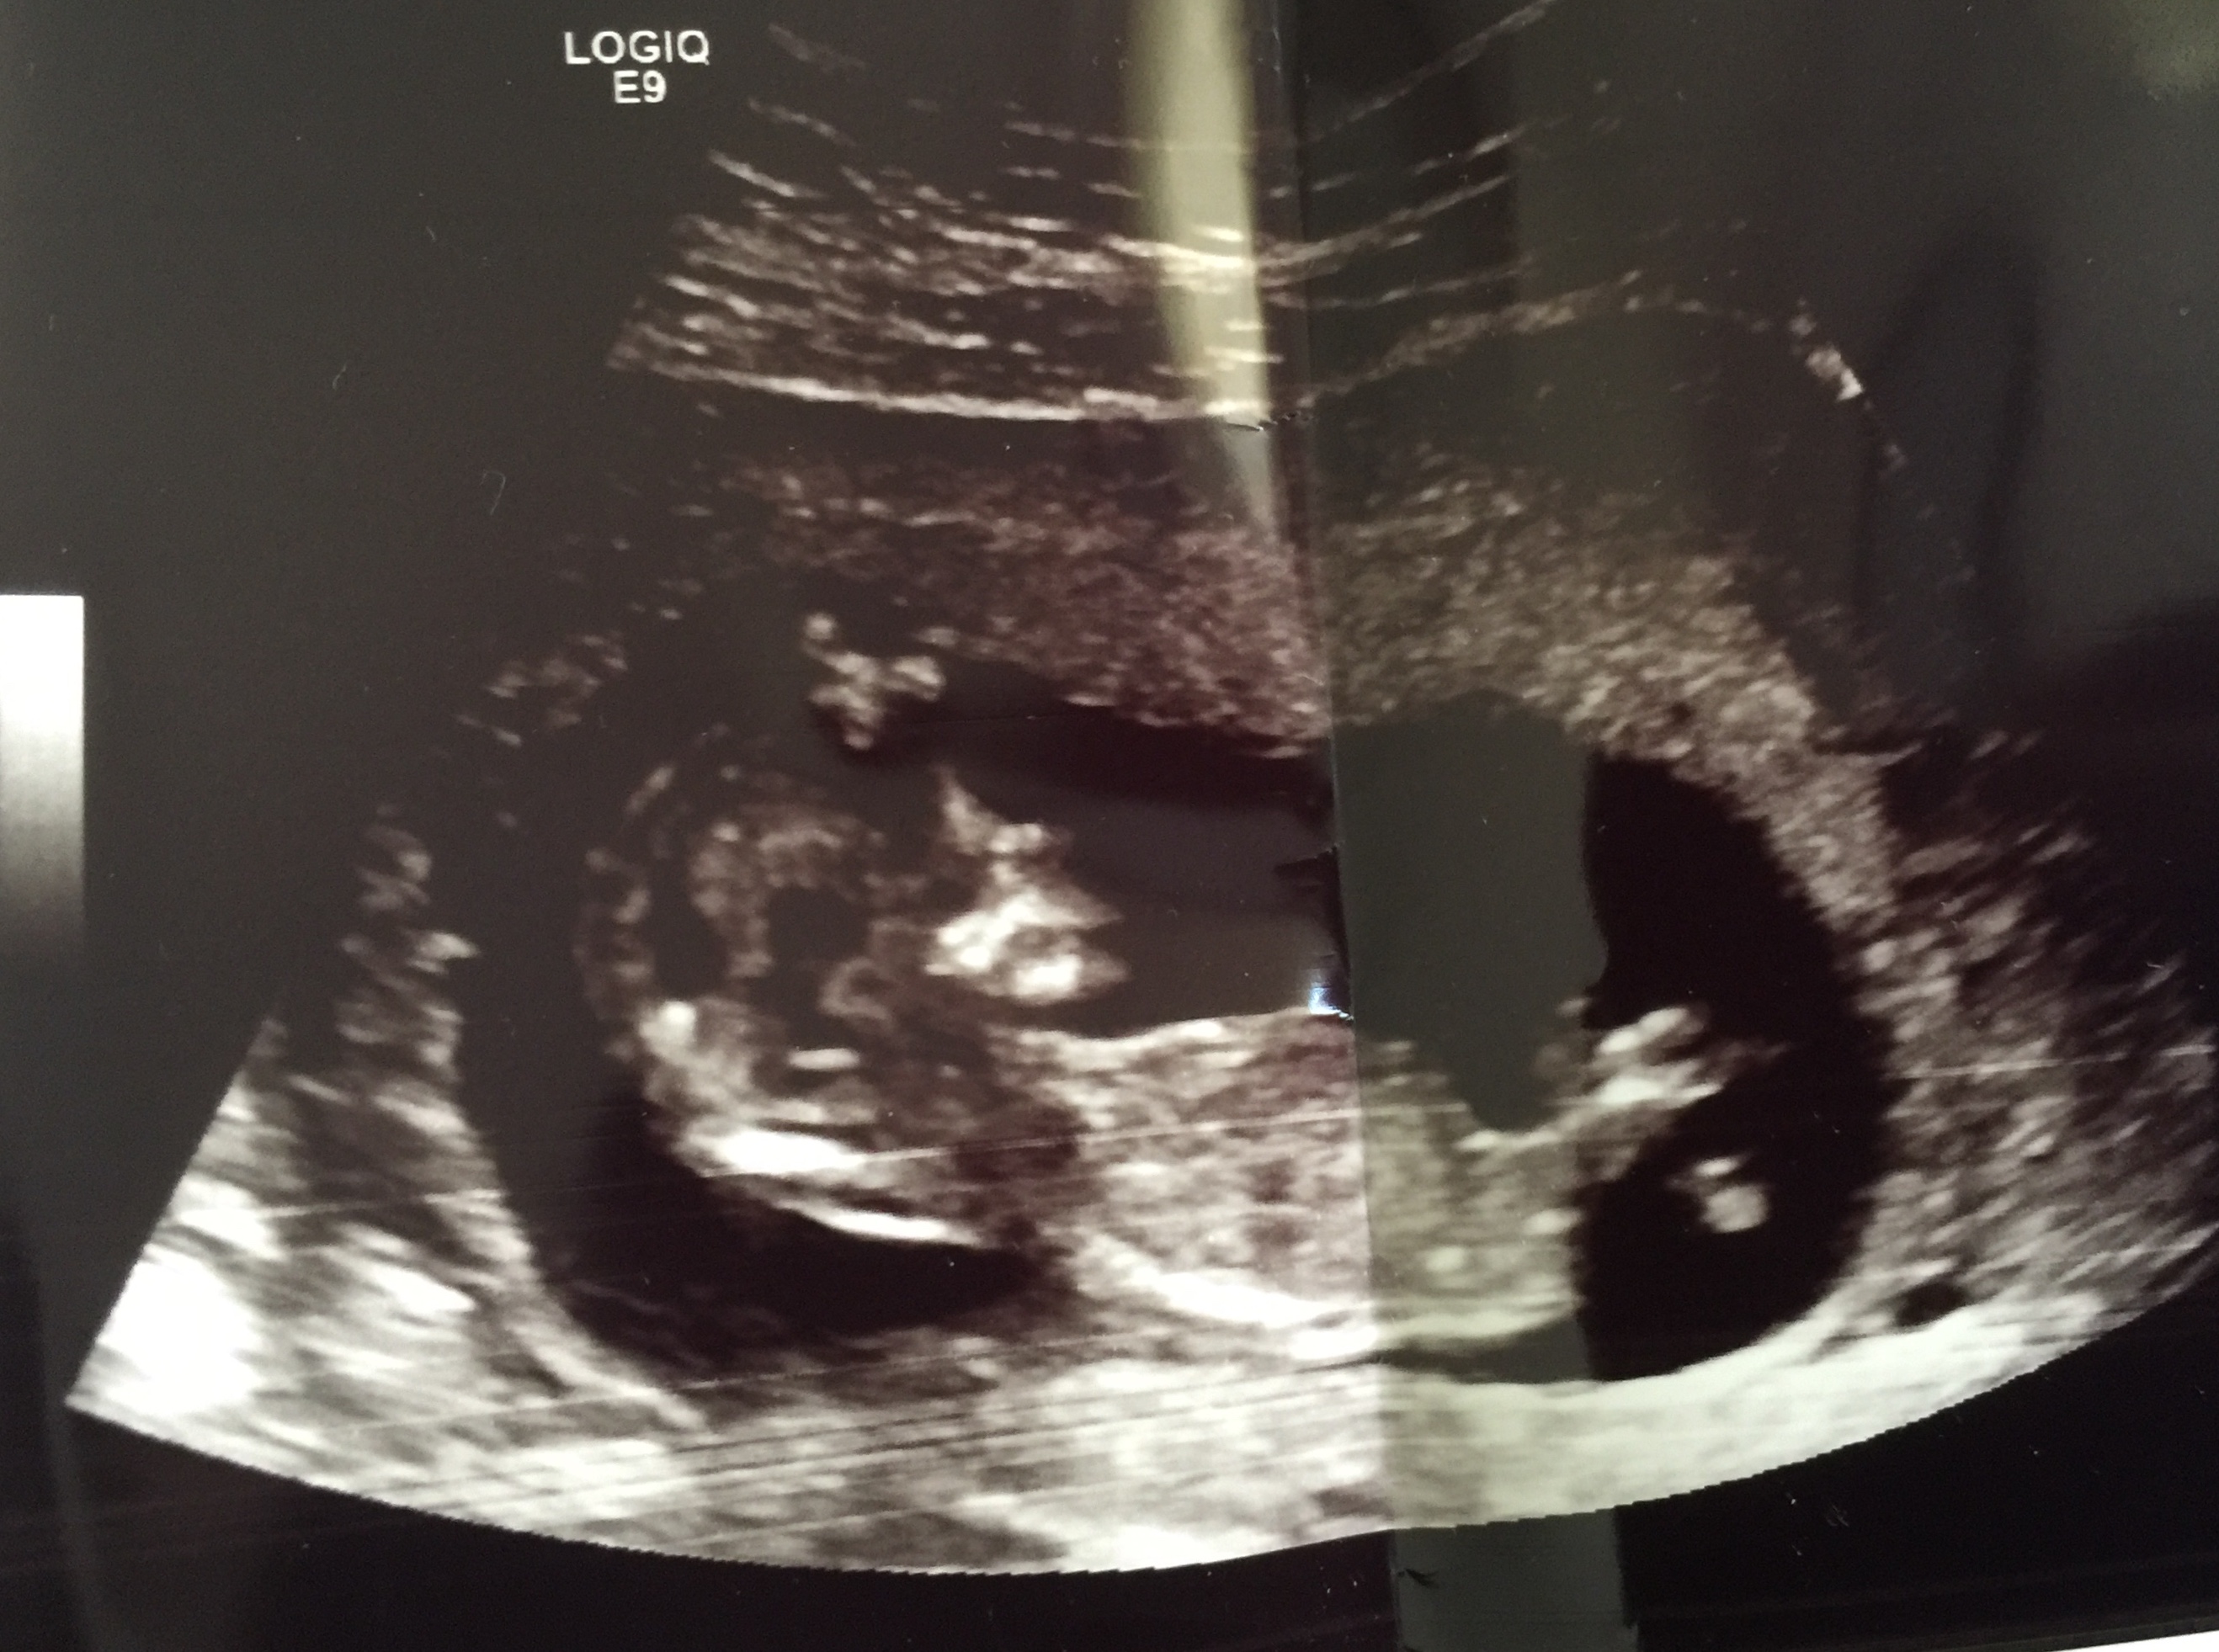

Hi! Asking for my sister. Is there a nub? Any guesses boy or girl would be very appreciated. :)

No nub for me to guess on sorry but I'm not an expert. Do you have any others profile pics like this?

Can you guess this one 12.5 w